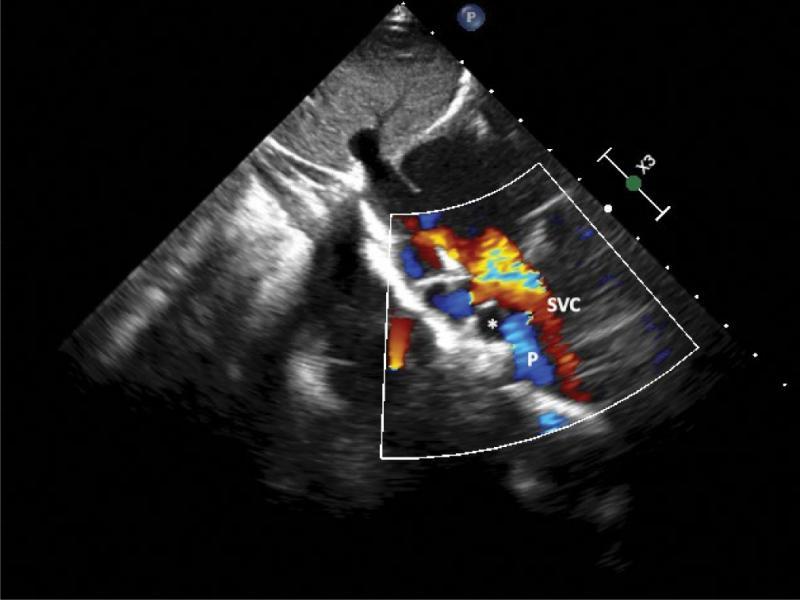

A supracardiac type of total anomalous pulmonary venous drainage (TAPVD) through a 12-millimeter-wide vertical vein with significantly dilated brachiocephalic vein and even more enlarged superior vena cava was diagnosed based on echocardiography (Fig. 1, Fig. 2, Fig. 3, Fig. 4, Fig. 5), and confirmed using CT angiography (Fig. 6, Fig. 7, Fig. 8). A 10 mm secundum atrial septal defect permitted a relatively unrestricted right-to-left atrial flow, and thus the survival of the patient. The right atrium and right ventricle were also enlarged. Echocardiographic signs of pulmonary hypertension were present. The marked dilatation of the SVC and unusual, turbulent flow pattern within this vessel, which was detected on ECHO, suggested that the right upper pulmonary vein drained separately to the SVC. This suspicion was not confirmed by either CT angiography or direct surgical inspection.

The same view as in Fig. 4, flow coded with color. Two streams of flow are visible within the SVC: typical inflow from SVC to the RA, coded in red, and, appearing at the level of SVC/RPA crossing, directed oppositely – coded in blue. Both the direction and possible site of connection suggest an additional pulmonary vein joining the SVC